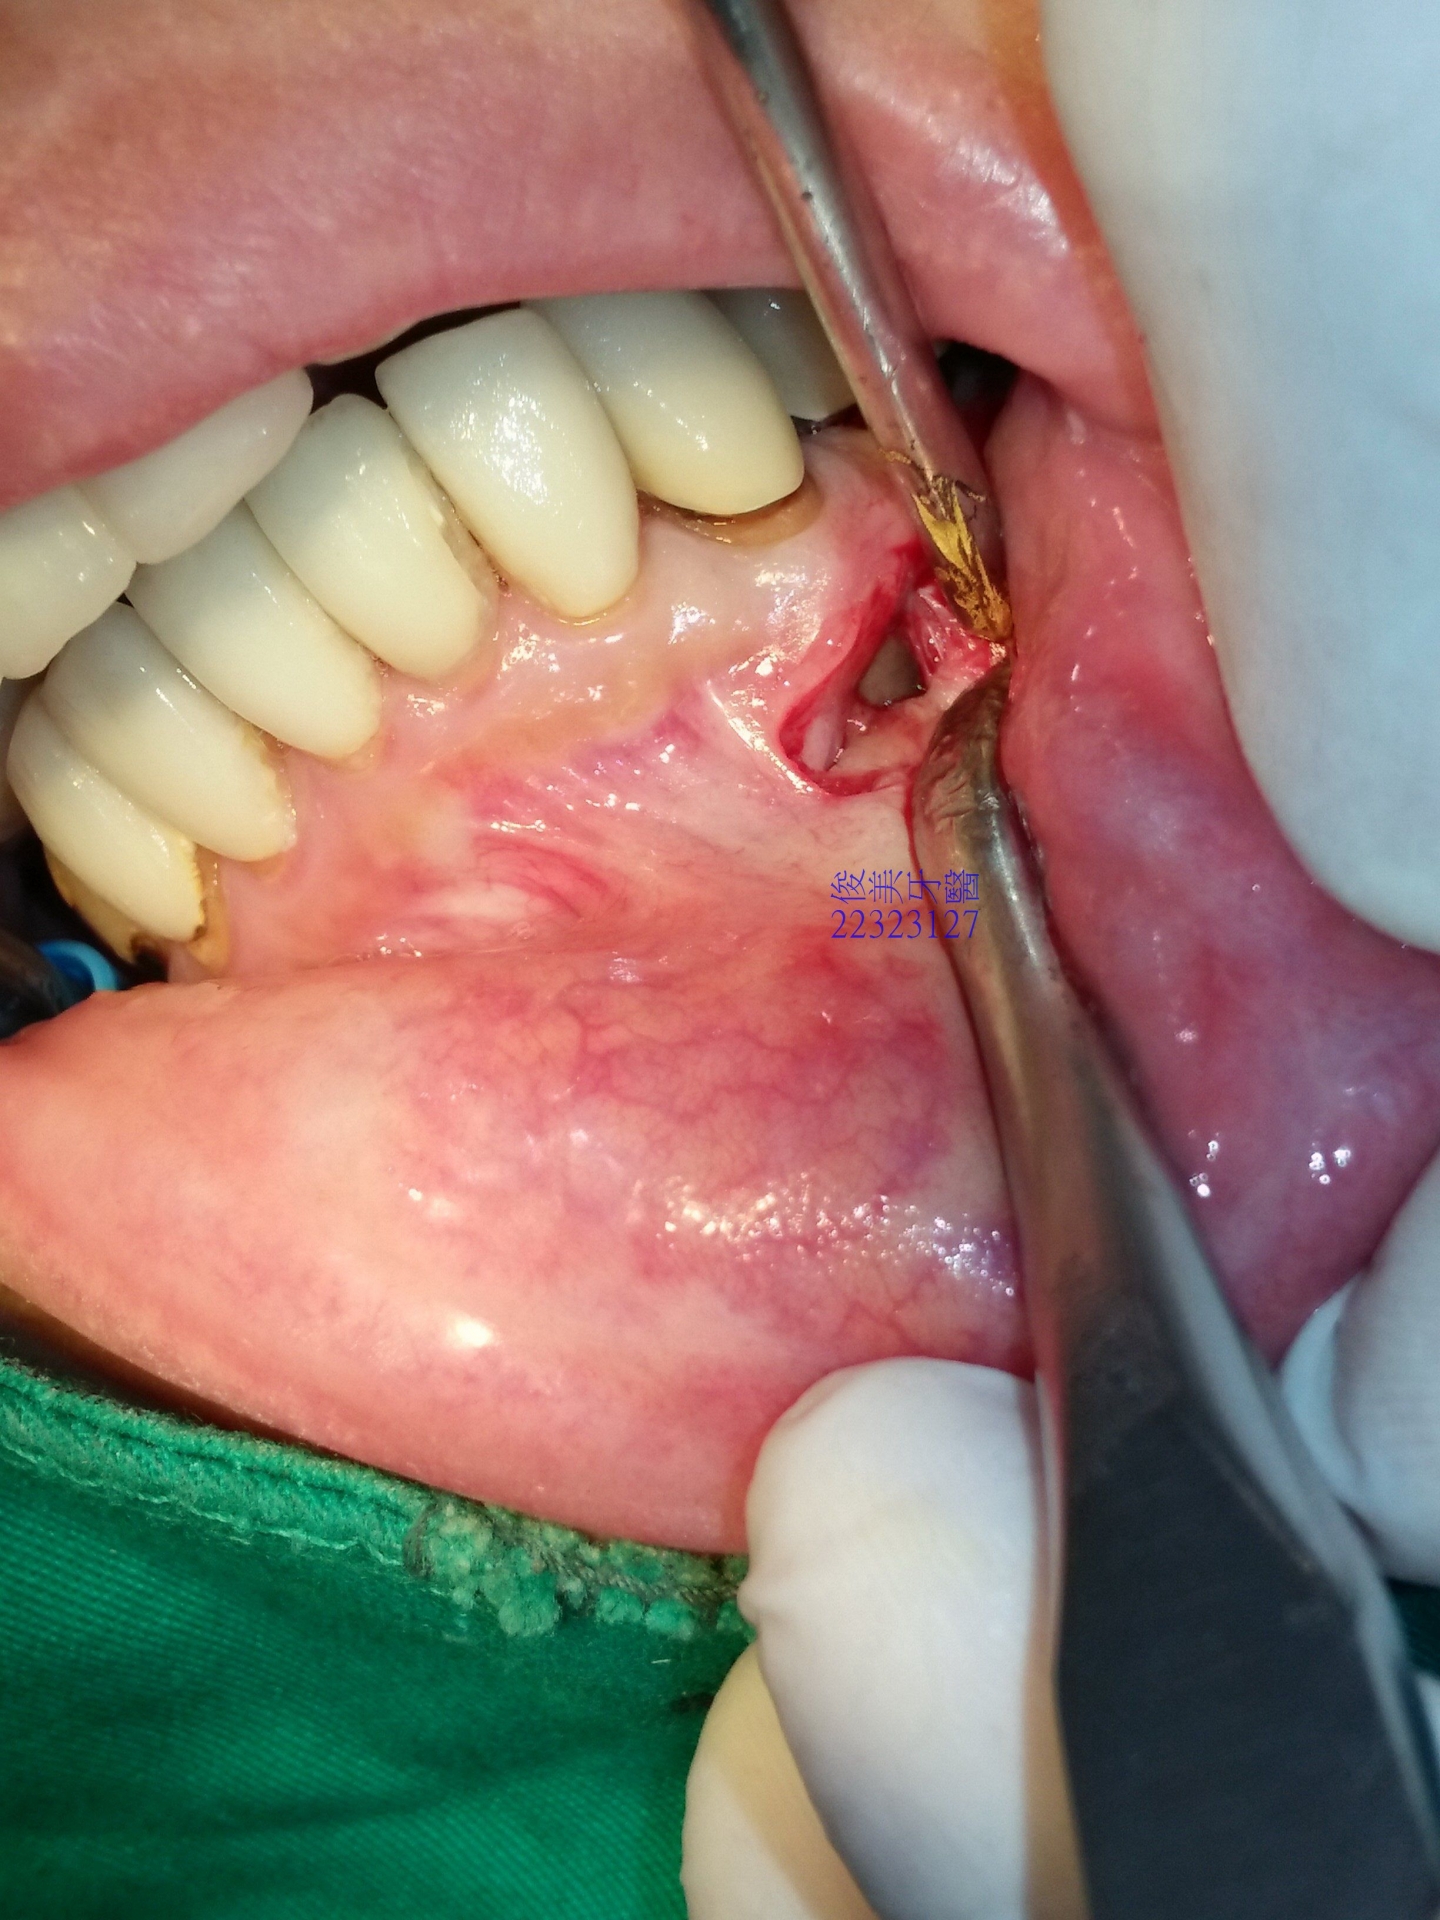

將異常生長組織刮除乾淨.....

置入人工骨粉,再縫合。